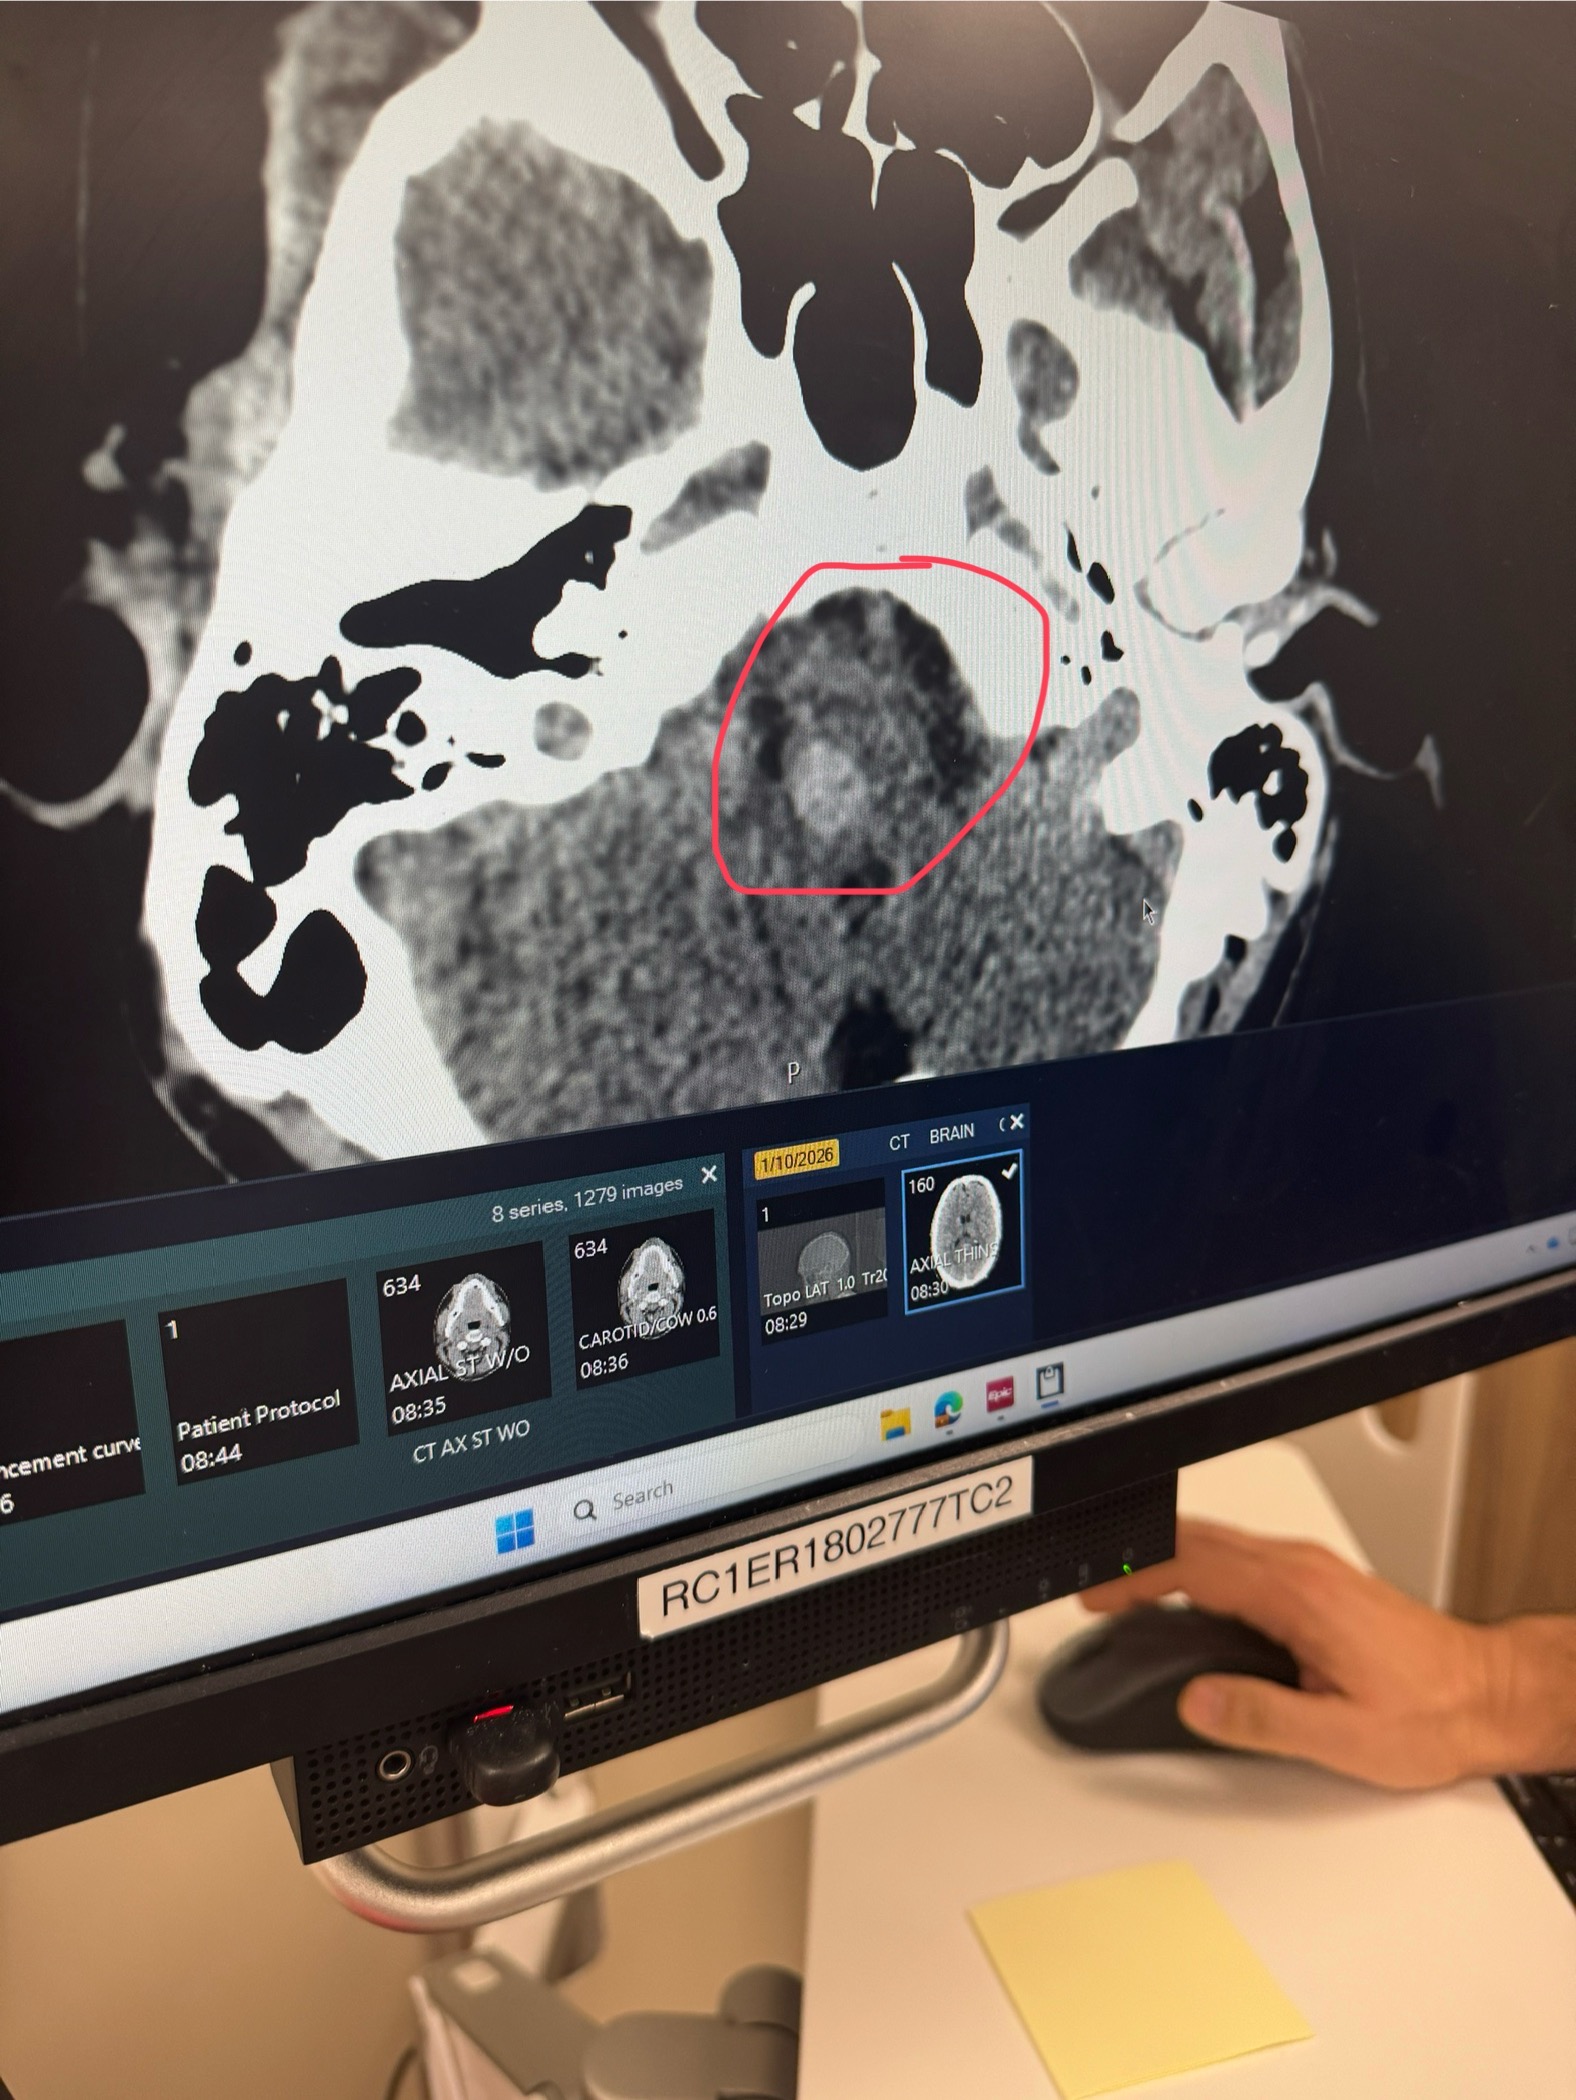

Rayce recently suffered a brain bleed in the medulla of his brainstem that caused stroke like symptoms. He is currently hospitalized at Monument Health in Rapid City and will be there for weeks, followed by a long road of rehabilitation.